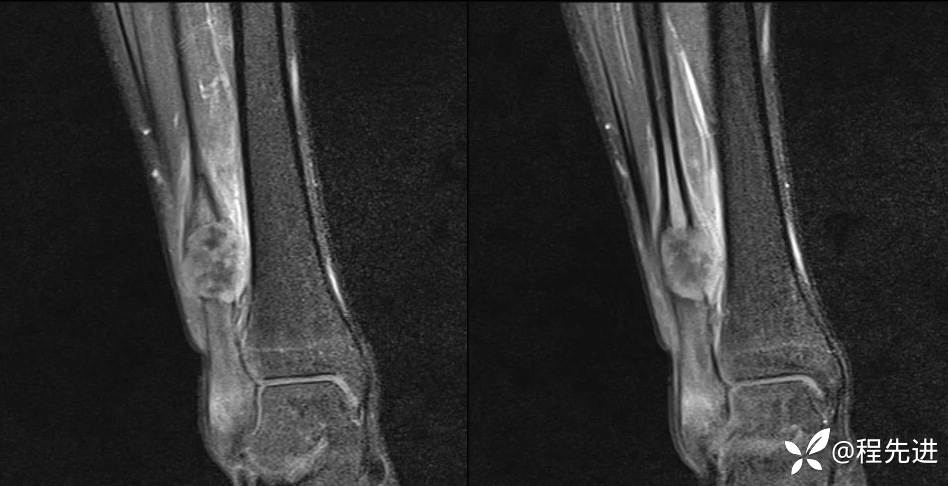

MR

T2

T1

T1+C